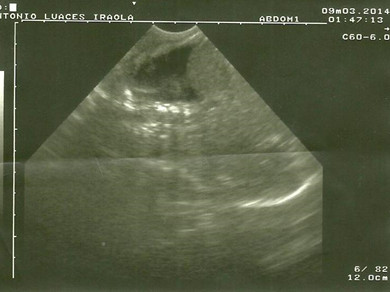

Volver a los detalles del artículo Quilotórax neonatal